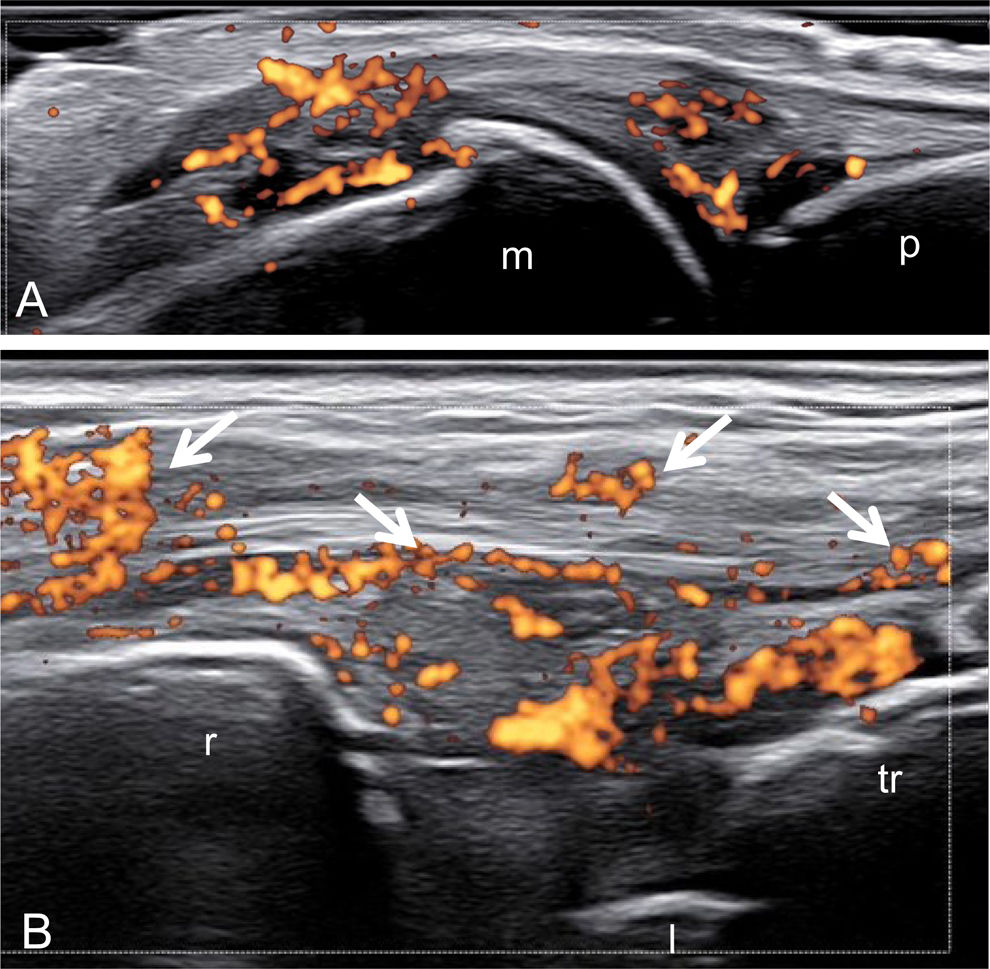

Synovitis (Figs. 1 and 2): Joint involvement is variable in PsA and SpA. Ultrasound findings in these conditions are not specific, as it may also occur in patients with other inflammatory conditions, such as RA [20]. US can detect subclinical synovitis, which is quite common in early PsA [21]. Similar findings have been observed in patients with psoriasis with joint symptoms, where up to 50% of clinically inactive joints had positive US findings for synovitis with or without Doppler activity [22].

Fig. 1.Psoriatic arthritis. Wrist. Right (A)–left (B) comparison. Ultrasound images acquired using a dorsal median longitudinal A. Evident active synovitis of the wrist. B. Subclinical mild active synovitis of the radio-carpal joint (arrow). r=radius; l=lunate bone; c=capitate bone; m=base of the third metacarpal bone.